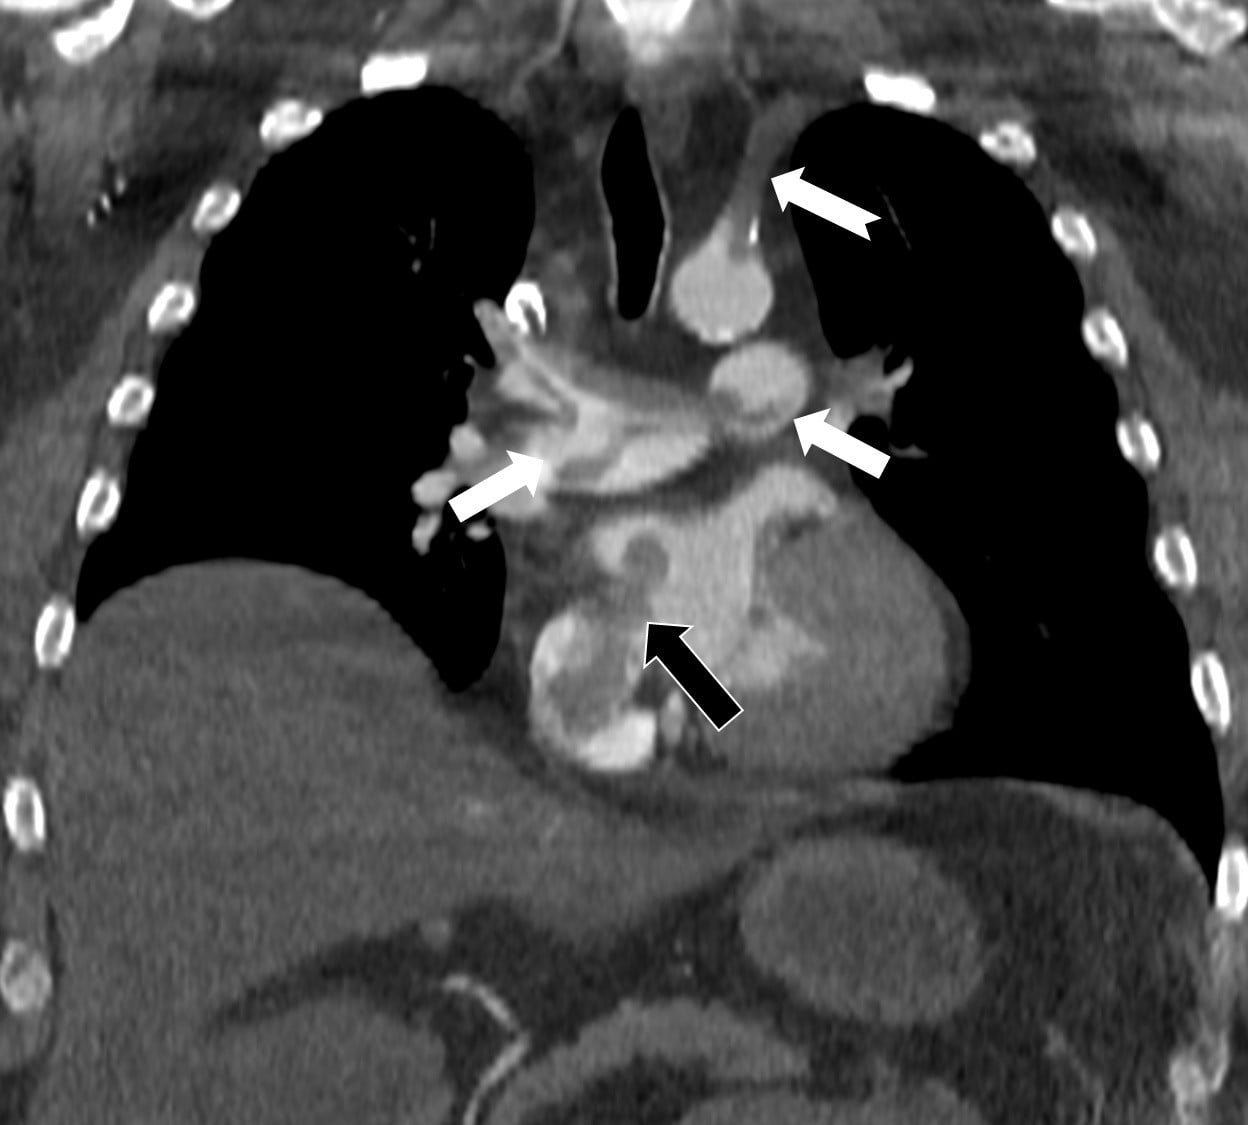

Çalışmada kullanılan bilgisayarlı tomografi anjiyografisi, toplar damarlardan kaynaklanan pıhtının akciğer damarlarını tıkamasının yanında, kalpteki delik nedeniyle pıhtının sağ taraftan sol tarafa geçerek ana atardamara ulaştığını ve sol kol damarını tıkadığını gösterdi. Bu tablo, klasik akciğer embolisinin ötesinde paradoks emboli riskini belgeledi.

Çalışmada, nedeni bilinmeyen pıhtı atmalarında kalpteki gizli deliklerin mutlaka araştırılması gerektiği belirtildi. Ayrıca ekokardiyografi ve bilgisayarlı tomografi tetkiklerinin erken ve doğru tanı koymada hayat kurtarıcı rol oynadığına dikkat çekildi.